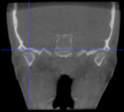

Three points determined the Acta plane: O, F right (FR), and F left (FL) (Table 2). Point O is the midpoint between the most craniodorsal point of the dorsum Sella and the most posterior dorsal point of the Basion in the midsagittal plane (Figure 1). Both points F are a result of the intersection between two lines: the line that connects the most inferior points of the lower orbital margins, right and left, and a line perpendicular to this line that runs through the most external points of the orbital margins, right and left (Figure 2). The new transverse reference plane, the Acta plane (Figure 2), is created by connecting the O-point (Figure 1) with FR and FL (Figure 2).

Figure 2.

(A) Construction of the F-points (right and left), frontal view. The F-points are originated from the intersection between the line connecting points A (the most inferior point of the lower orbit) and the perpendicular line to it that passes through points B (most external/lateral point of the Orbita). (B) Transverse view of the ACTA plane.